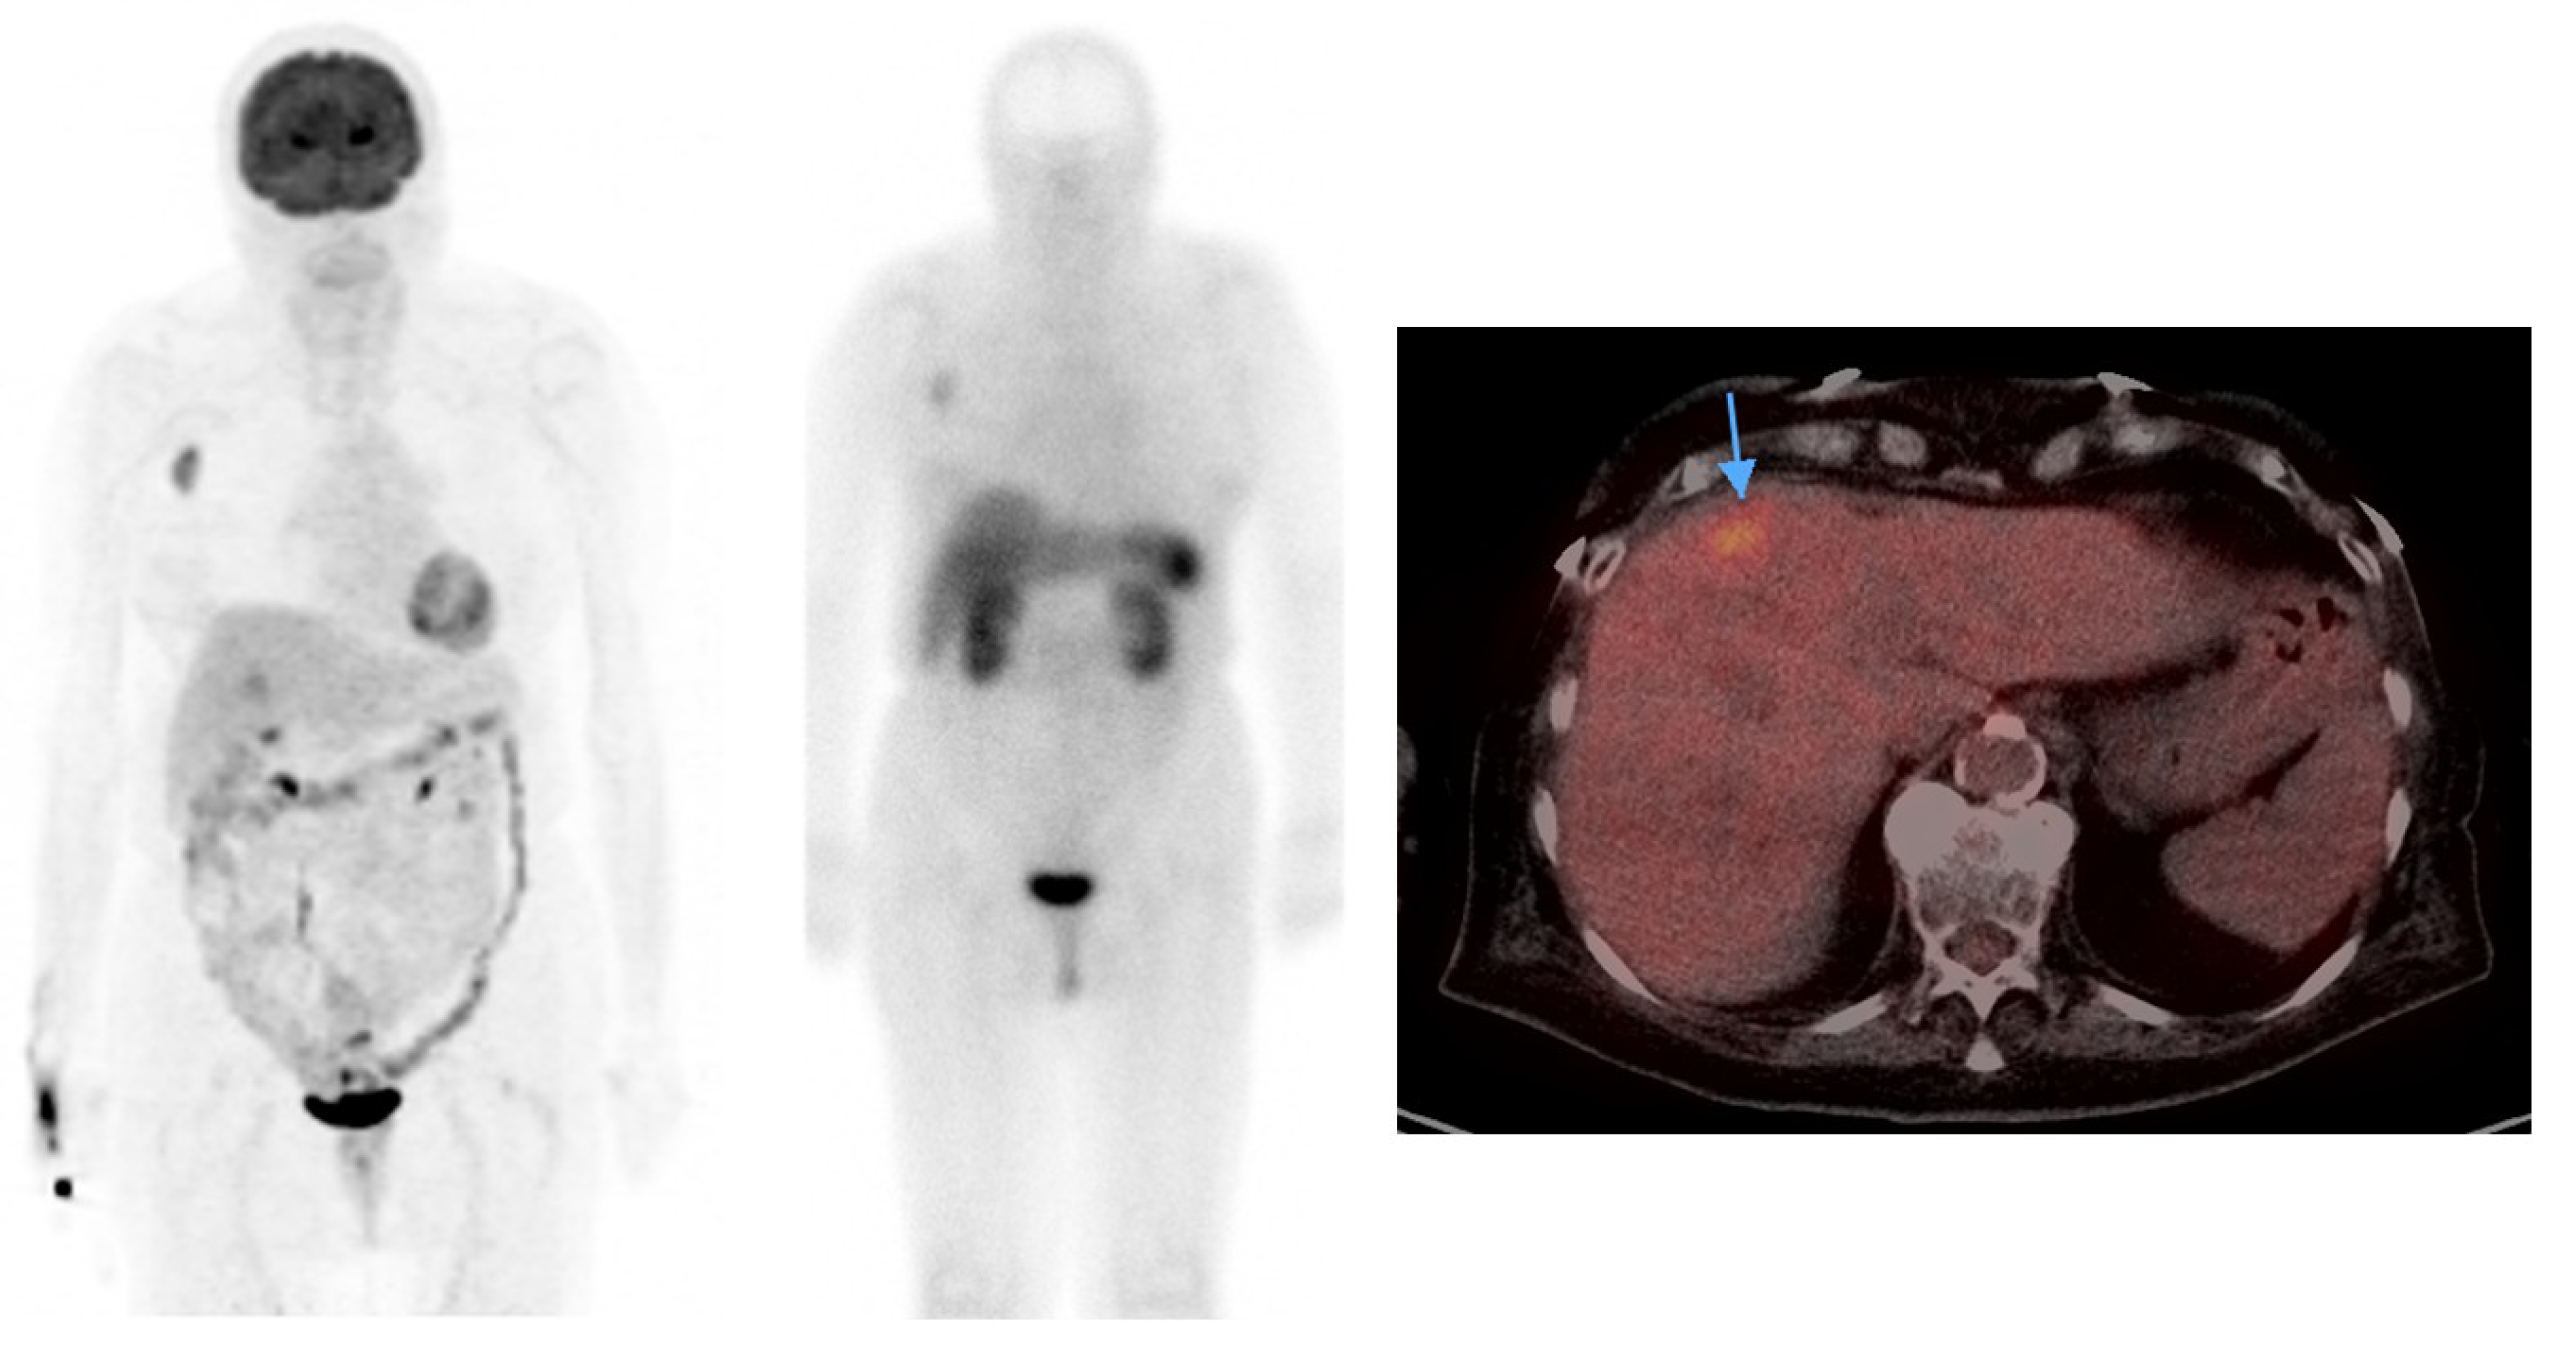

- Epstude, M.; Tornquist, K.; Riklin, C.; di Lenardo, F.; Winterhalder, R.; Hug, U.; Strobel, K. Comparison of 18F-FDG PET/CT and 68Ga-DOTATATE PET/CT imaging in metastasized Merkel cell carcinoma. Clin. Nucl. Med. 2013, 38, 283–284. [Google Scholar] [CrossRef]

- Schmidt, M.C.; Uhrhan, K.; Markiefka, B.; Hasselbring, L.; Schlaak, M.; Cremer, B.; Kunze, S.; Baum, R.P.; Dietlein, M. 68Ga-DOTATATE PET-CT followed by peptide receptor radiotherapy in combination with capecitabine in two patients with Merkel cell carcinoma. Int. J. Clin. Exp. Med. 2012, 5, 363–366. [Google Scholar]